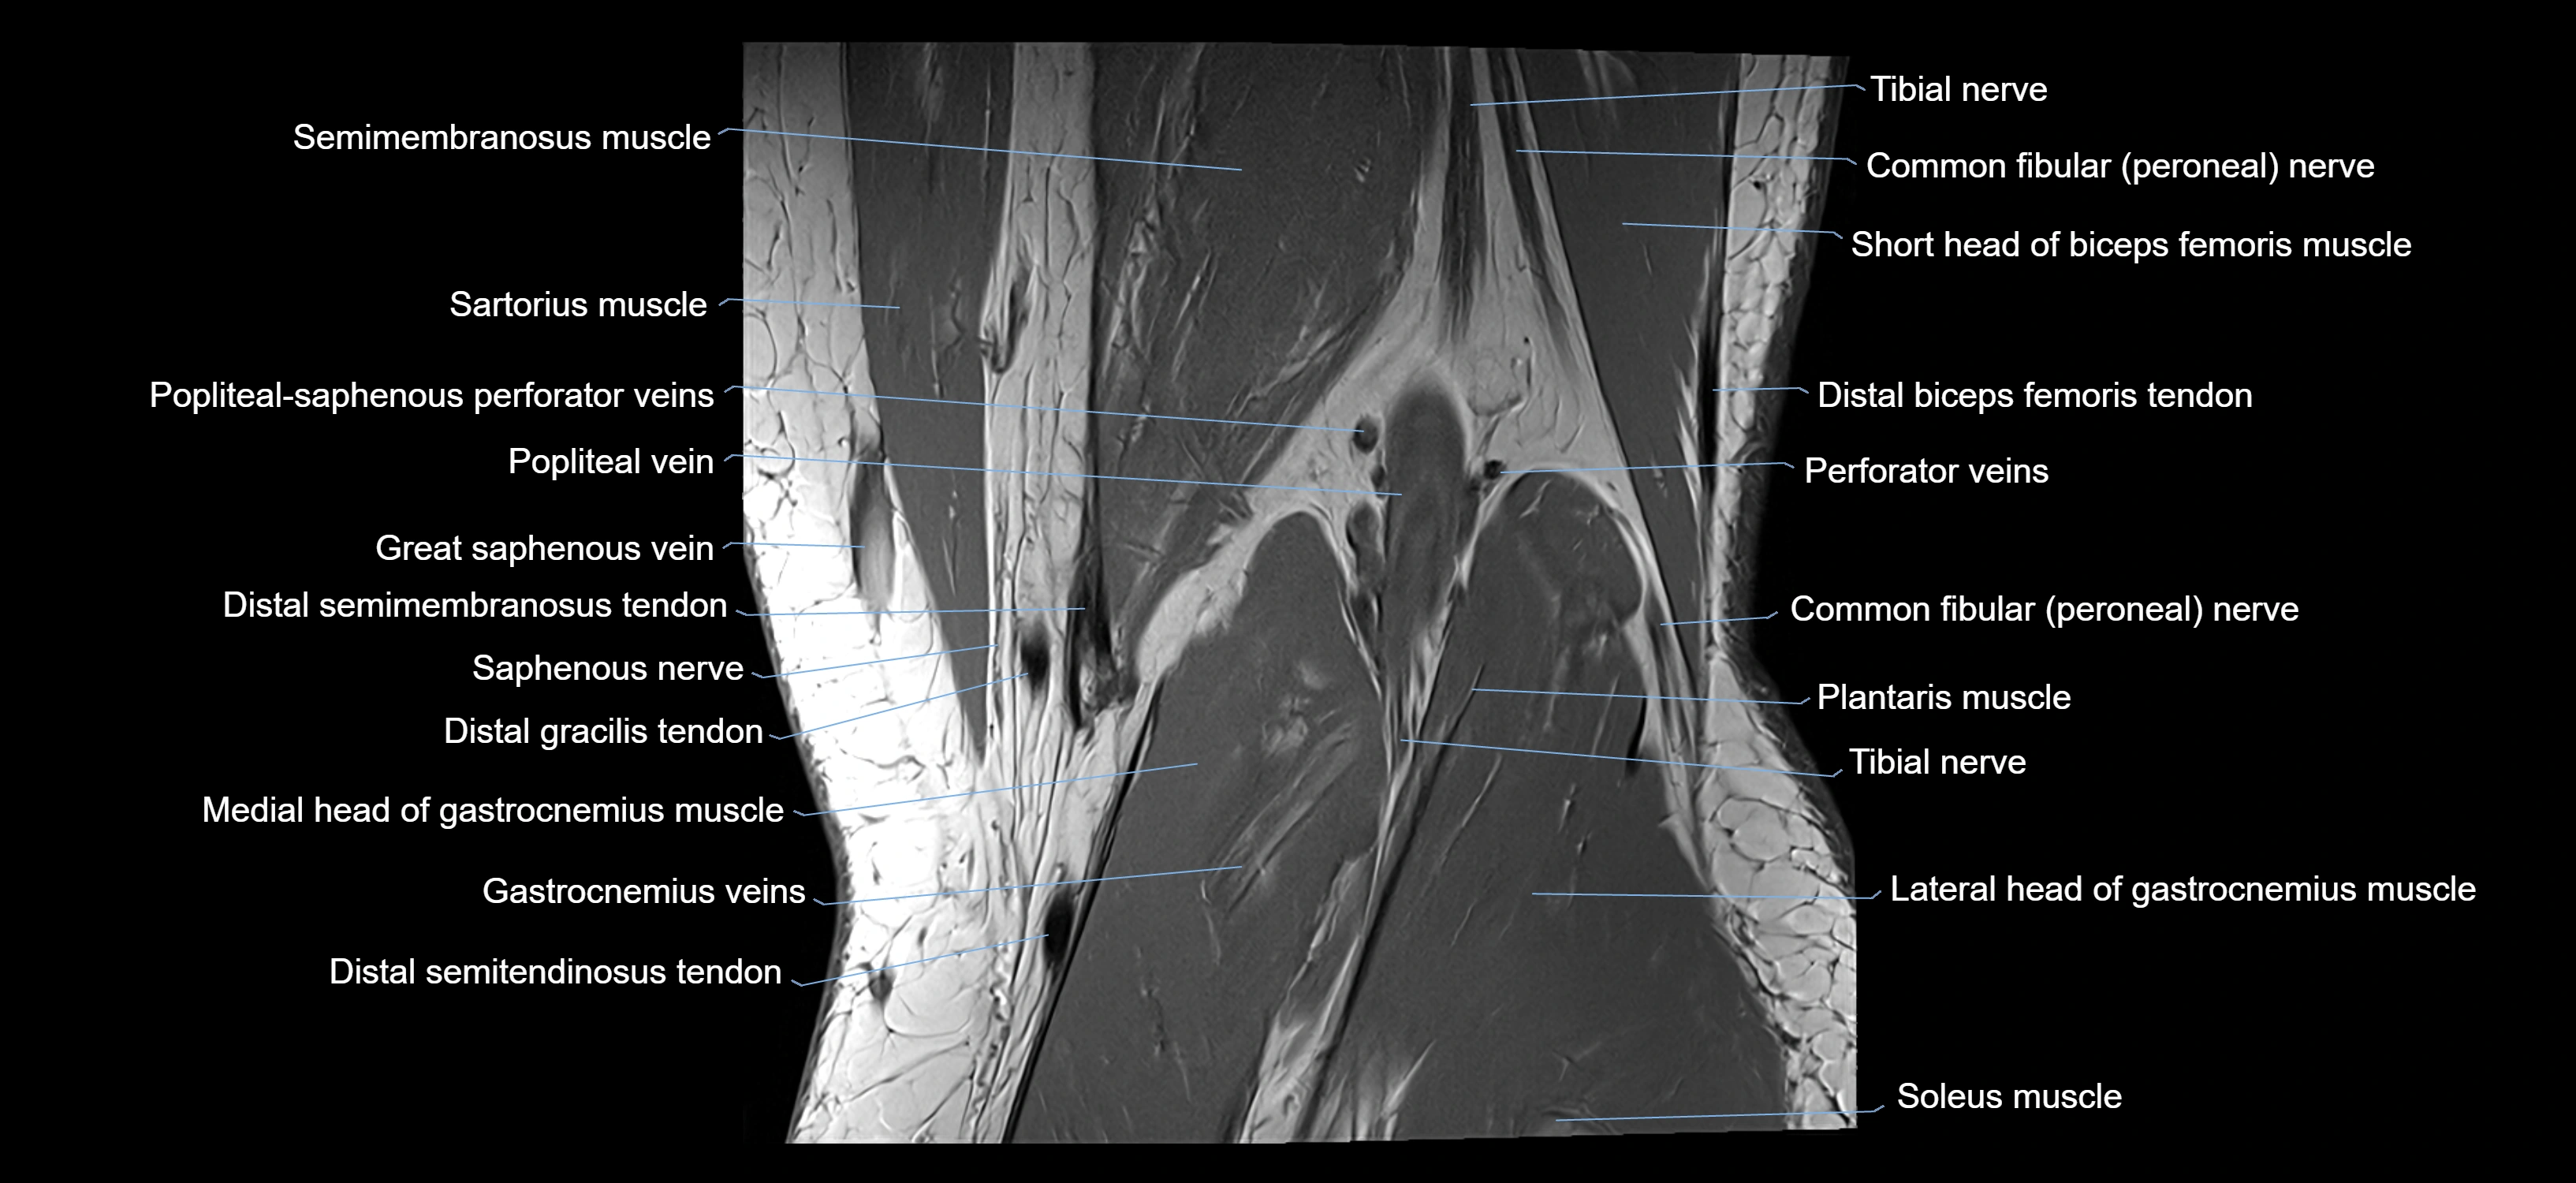

- Distal semimembranosus tendon

- Distal semitendinosus tendon

- Gracilis tendon (Distal)

- Lateral head of gastrocnemius muscle

- Medial head of gastrocnemius muscle

- Plantaris muscle

- Popliteal vein

- Popliteal–Saphenous perforating veins

- Saphenous nerve

- Sartorius muscle

- Semimembranosus muscle

- Semitendinosus muscle

- Soleus muscle

- Tibial nerve